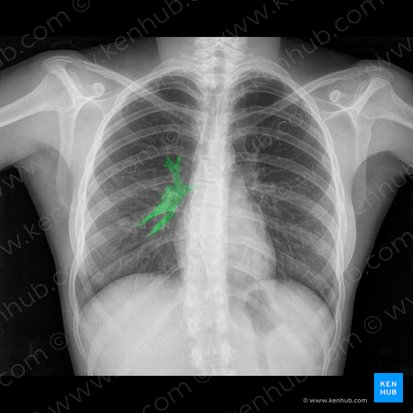

Ao nível do ângulo esternal, o tronco pulmonar divide-se nas artérias pulmonares direita e esquerda, que transportam o sangue desoxigenado do ventrículo direito do coração para os pulmões direito e esquerdo, respectivamente. Cada artéria pulmonar faz parte do hilo de seu respectivo pulmão e se divide em artérias lobares secundárias. As artérias lobares então se dividem em artérias segmentares terciárias. As artérias seguem o padrão de ramificação dos brônquios, na maioria das vezes cursando anteriormente a eles.

As artérias brônquicas se originam da aorta torácica, e carregam sangue oxigenado para os tecidos pulmonares e pleura visceral, cursando ao longo da superfície posterior dos brônquios. A aorta torácica dá origem às artérias brônquicas esquerdas, enquanto a única artéria brônquica direita emerge de uma das artérias intercostais posteriores superiores ou da artéria brônquica superior esquerda. Essas ramos se anastomosam com ramos das artérias pulmonares, formando uma rede arterial ao longo do tecido pulmonar.